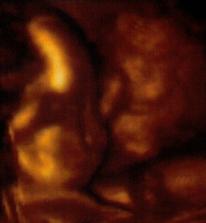

Po prvním neúspěchu začínáme znovu a doufáme, že i na nás se štěstíčko brzo usměje🙂***Máme novou naději🙂))) 30.11.2008 objeveny || na Mamatestu. Ihned nasazen Duphaston na podporu těhu.***21.12.2008 kontrola na pohotovosti kvůli špinění, od 1.1.2009 hospitalizace v nemocnici. Vše je ale naštěstí v pořádku.***Od ledna pravidelné kontroly po 14 dnech u své doktorky.***Poslední kontrola 6.2.2009 - mimi pěkně roste, jen se nechtělo rozbalit z klubíčka, takže nevíme, kolik měříme. Zato drobek pořád zvedal ruce a chytal se za hlavičku🙂***Kontrola 20.2.- pouze pohmatem***2.3. odebrána krev na tripple testy - vše je v pořádku.***27.3. na UTZ zjištěno, že nejspíš čekáme HOLČIČKU, co je hlavní...je zdravá🙂 Pořízena první fotečka a tatínek byl celou dobu přítomen, tak miminko poprvé viděl. Jinak pohyby cítím už 14 dní a podle UTZ nám byl posunut termín na 6.8.2009***14.4. jsme byli na 3D utz, krásný zážitek, malá pořád máchala ručičkama, strkala si je do pusy nebo si žmoulala oko***16.4. test na cukrovku - negativní (uf🙂)***Kontrola 27.5. - měříme kolem 40cm a vážíme 1560g. Potvrzená holčička🙂***Kontrola 26.6. - CS2, na porod to nevypadá. Odběry na protilátky a streptokoka. Od 29.6. řádná mateřská🙂